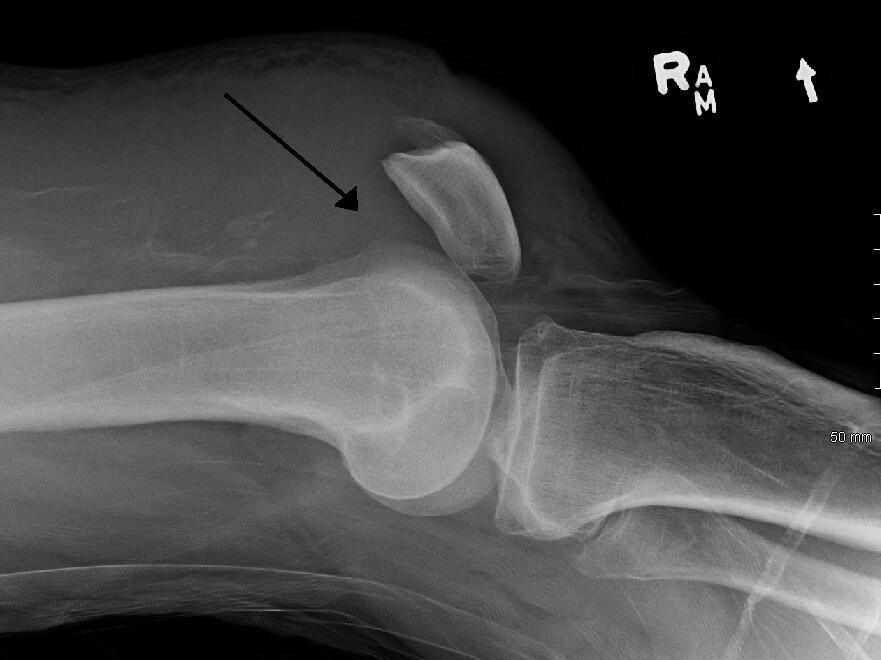

Clinique : extension du genou impossible et impossibilité de décoller le talon du lit.

Avis chirurgical pour traitement chirurgical.